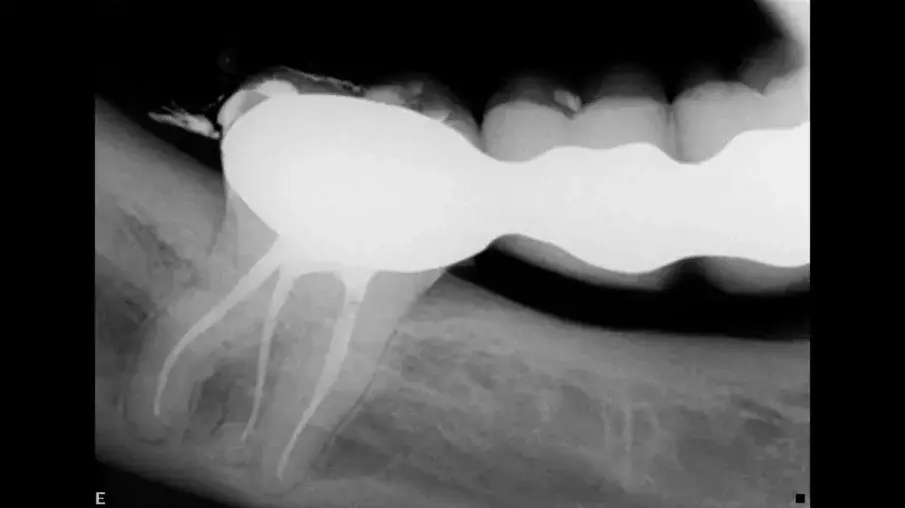

Пациент постъпва по спешност поради остра болка във втори горен молар. Това беше потвърдено при клиничния преглед. Направена е стандартна рентгенография (фиг. 1), която показва много сложна анатомия и калцирана пулпна камера. Историята на този зъб по думите на пациента е, че на него е бил поставен инлей, известно време след което се е появил дискомфорт, който е продължил няколко години без лечение. При контролния преглед му е било казано, че всичко е наред.

Фиг. 1 Предоперативна рентгенография, показваща много сложна кореноканална система и калцирана пулпна камера.